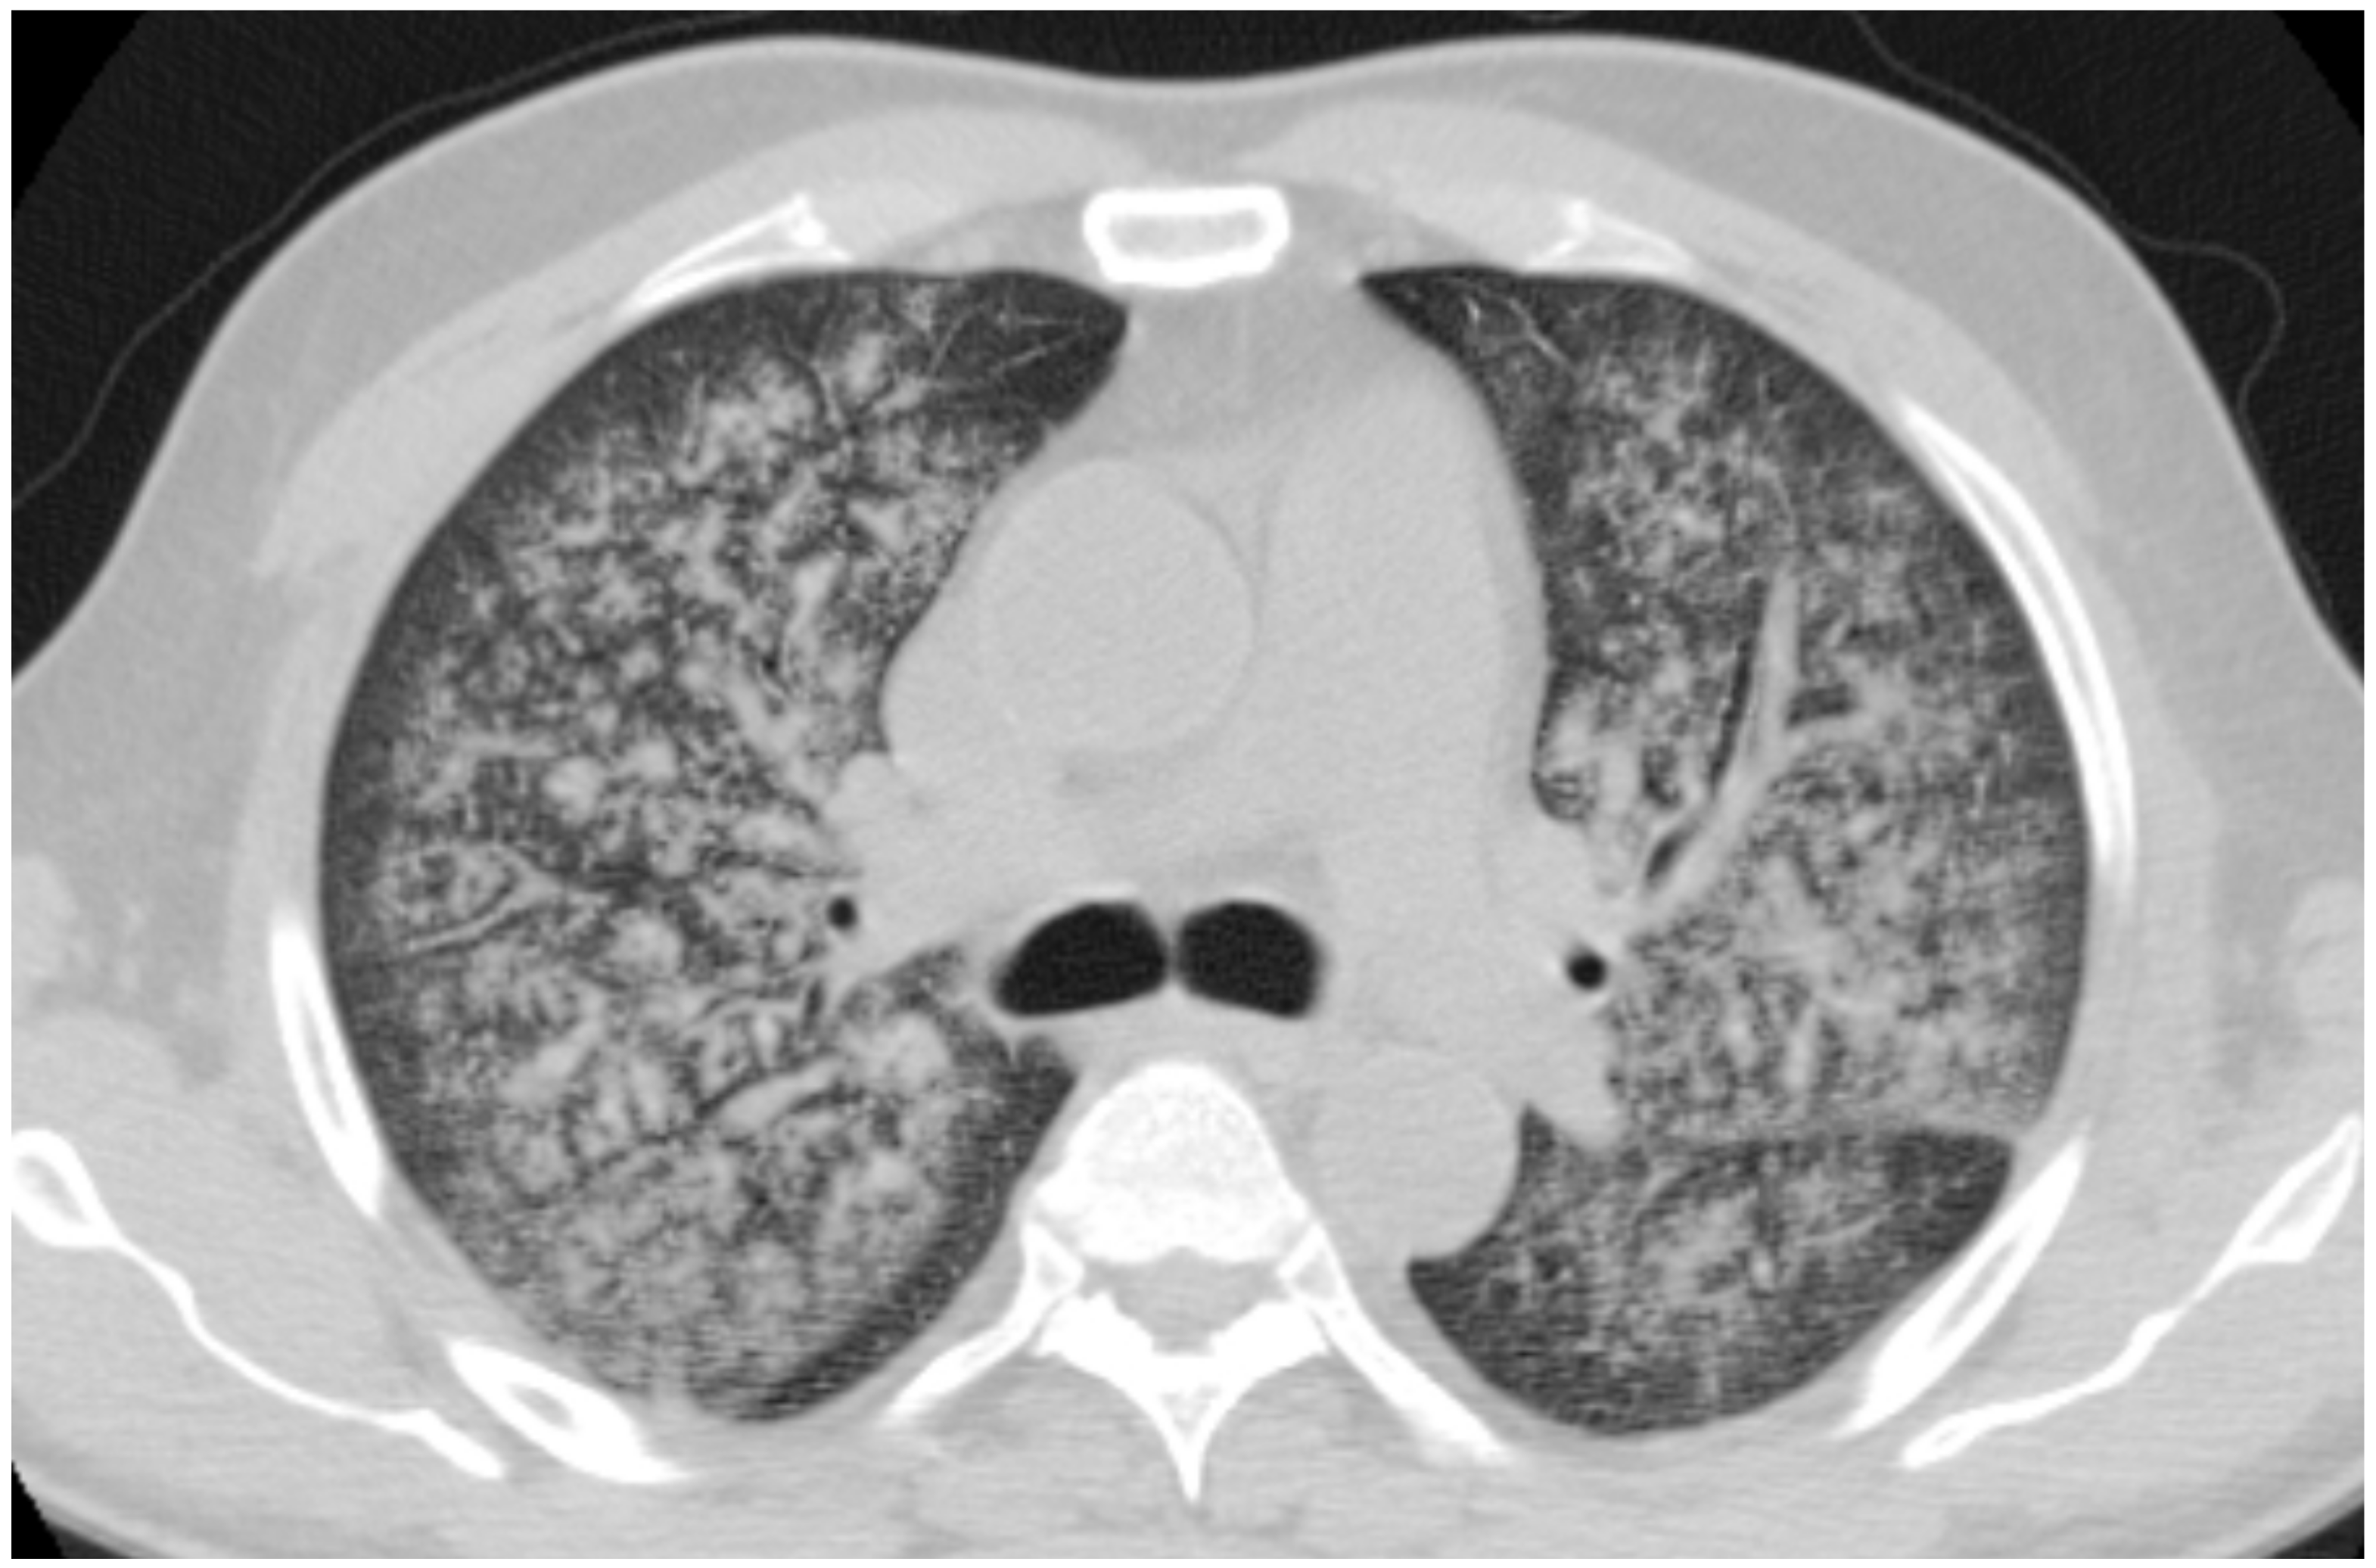

2.4. Granulomatosis with Polyangiitis (GPA-Wegener’s Disease)

| GPA | Solid nodules, GGOs due to hemorrhagic alveolitis (common); halo sign, crazy paving (less common) |